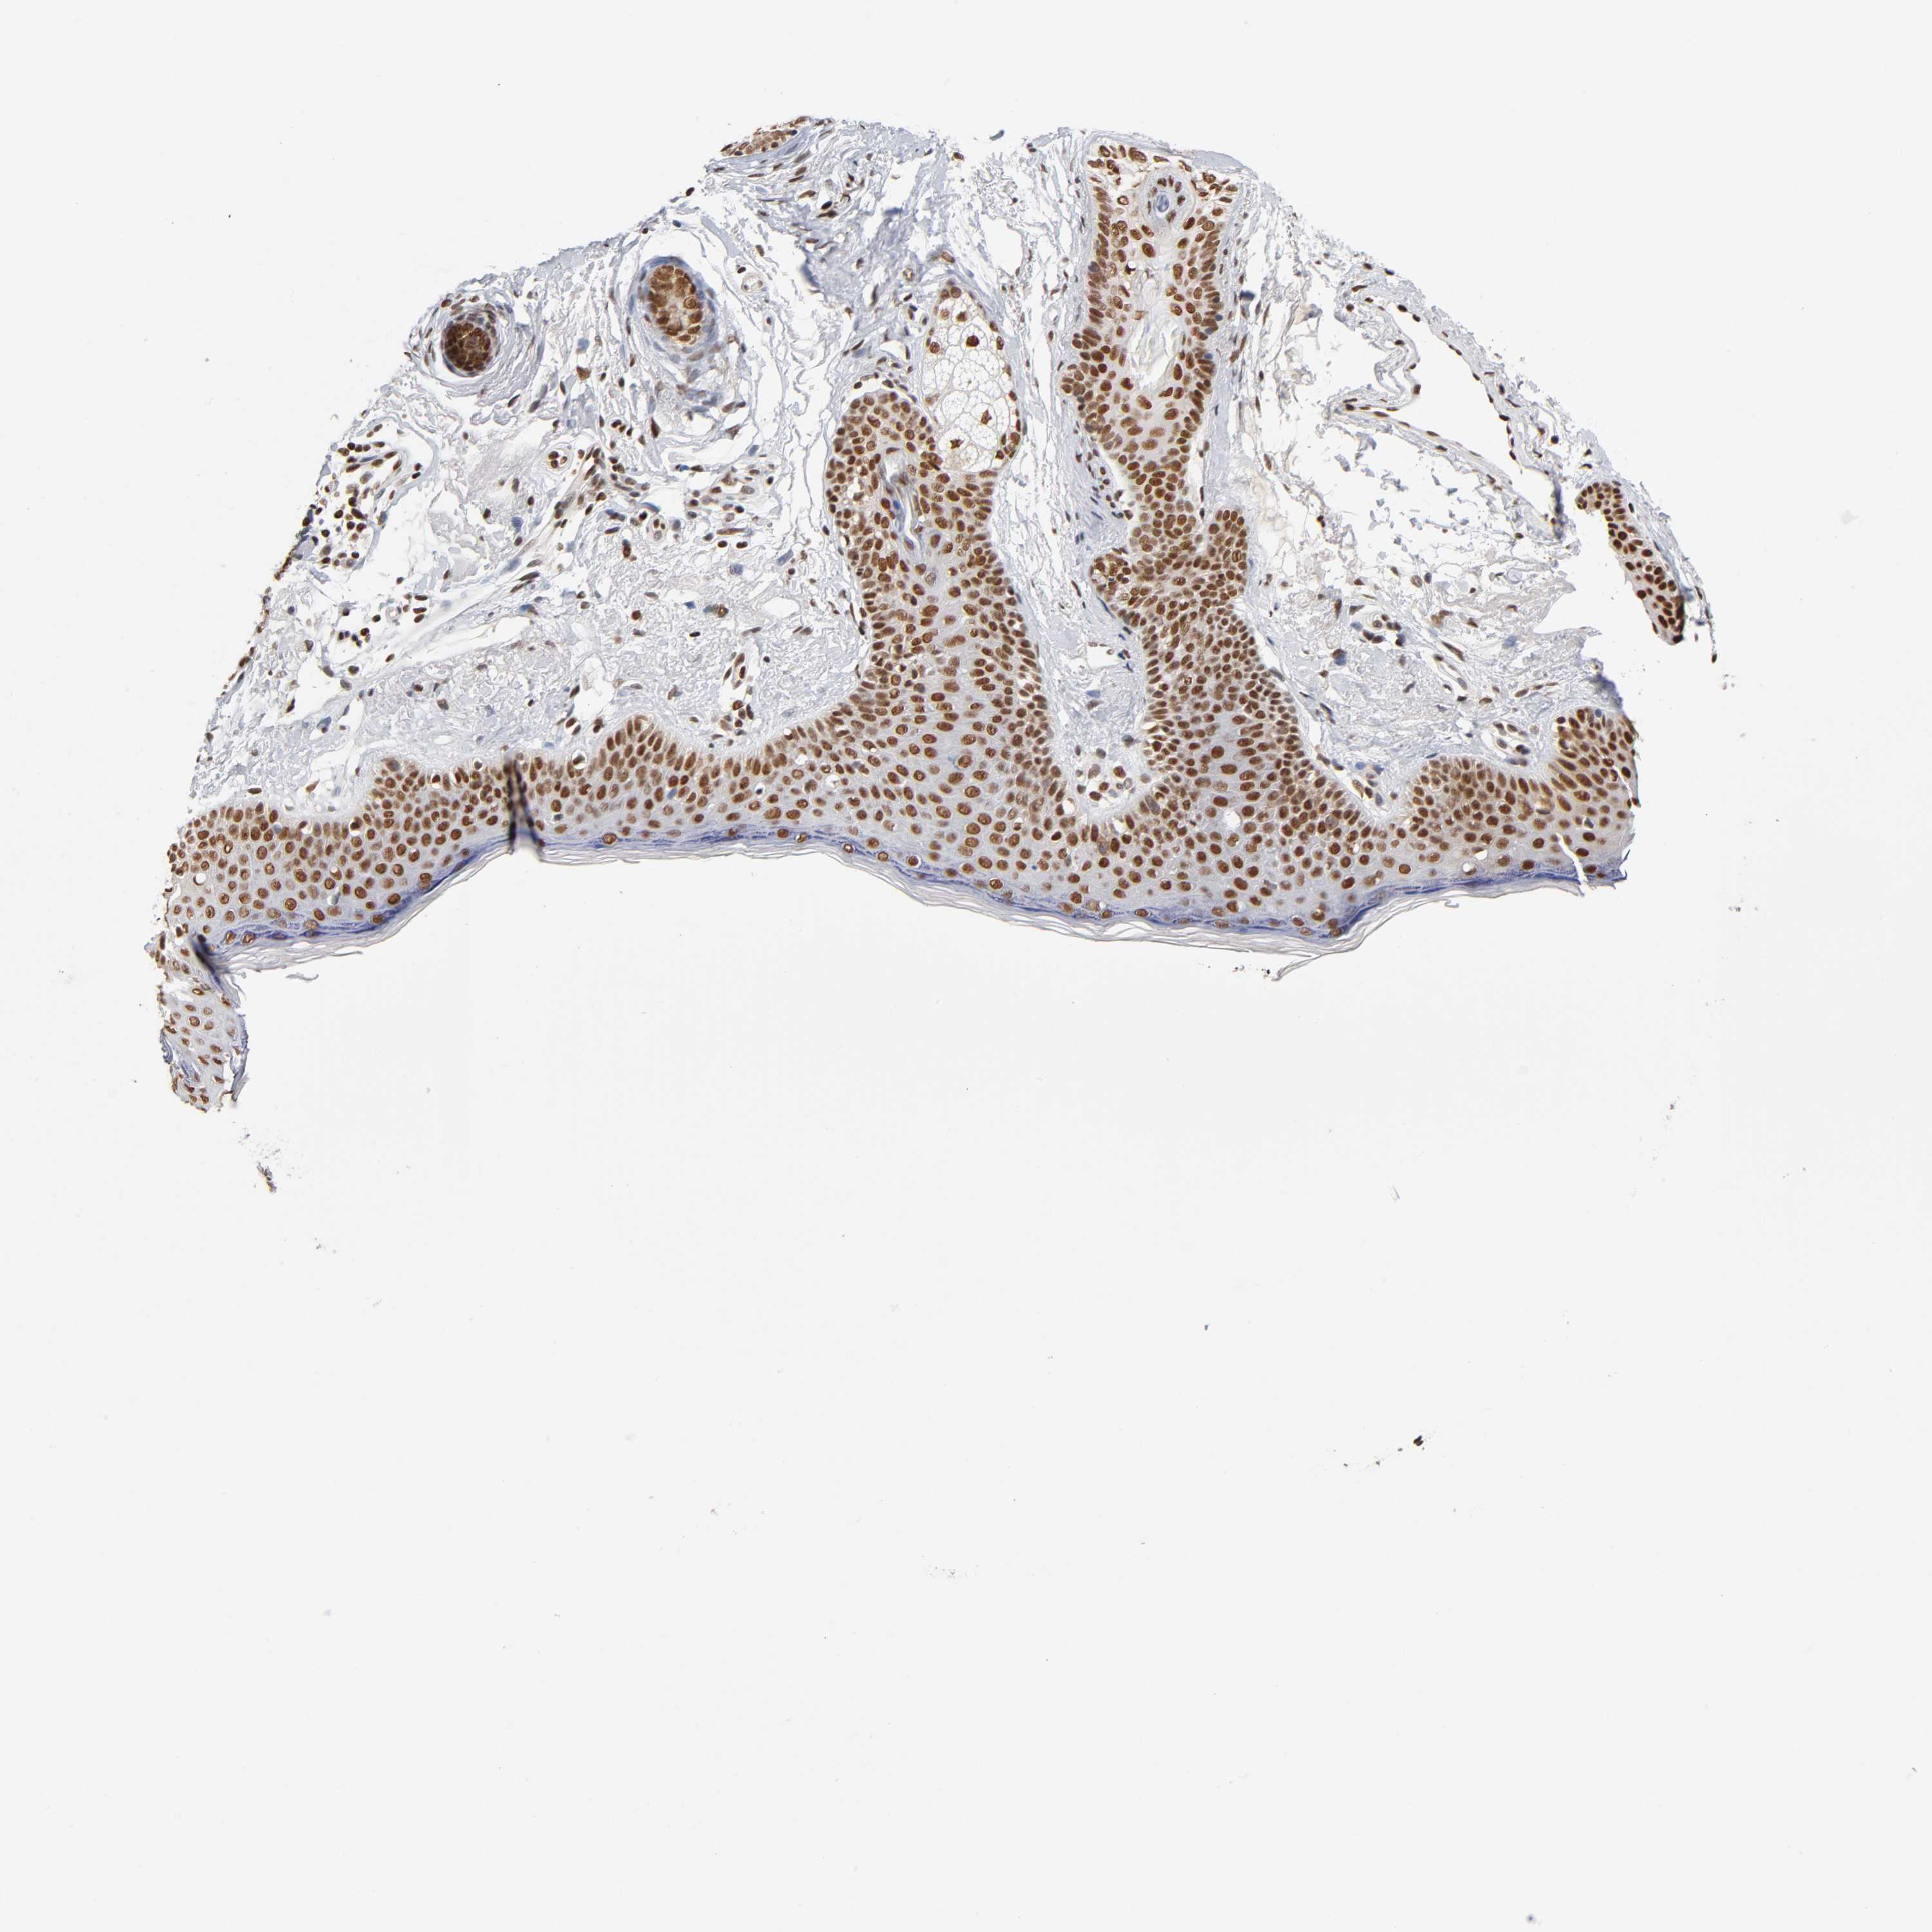

SKIN CANCER - Protein expressioni

A mouse-over function shows sample information and annotation data. Click on an image to view it in a full screen mode. Samples can be filtered based on level of antibody staining by selecting one or several of the following categories: high, medium, low and not detected. The assay and annotation is described here.

Antibody stainingi

Antibody staining in the annotated cell types in the current human tissue is reported as not detected, low, medium, or high, based on conventional immunohistochemistry profiling in selected tissues. This score is based on the combination of the staining intensity and fraction of stained cells.

Each image is clickable and will lead to virtual microscopy that enables deeper exploration of all samples and also displays staining intensity scores, fraction scores and subcellular localization as well as patient and tissue information for each sample.

Antibody HPA004752

Staining

High

Intensity

Strong

Quantity

>75%

Location

Nuclear

Squamous cell carcinoma, NOS

Basal cell carcinoma